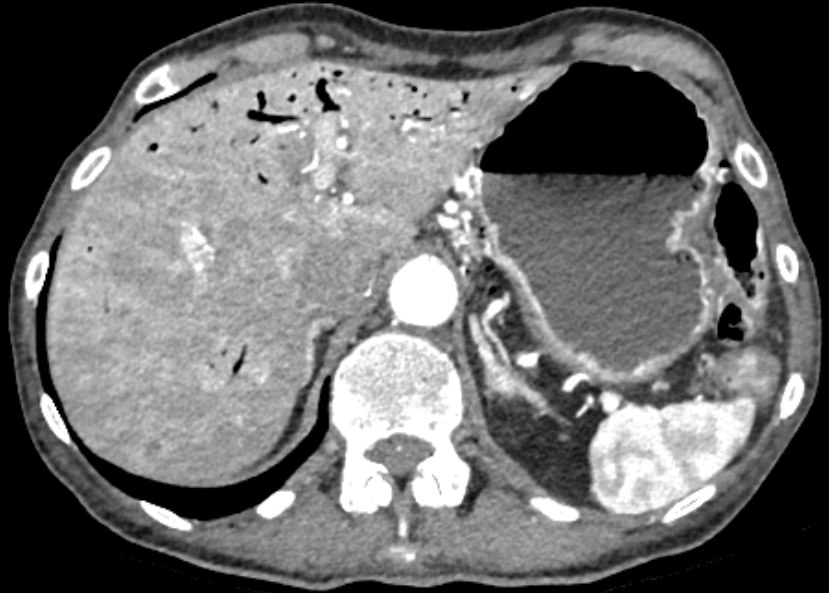

Помимо ожидаемой картины непроходимости были выявлены редкие и клинически значимые изменения:

газ в системе воротной вены (портальный пневматоз);

интрамуральный газ в стенке желудка;

тромбоз верхней брыжеечной вены;

локальный тромбоз верхней брыжеечной артерии.

Как отличить портальный пневматоз от пневмобилии на КТ?

Портальный пневматоз — газ располагается периферически, близко к капсуле печени.

Пневмобилия — газ локализуется центрально, ближе к воротам печени, не доходя до капсулы минимум на 2 см.